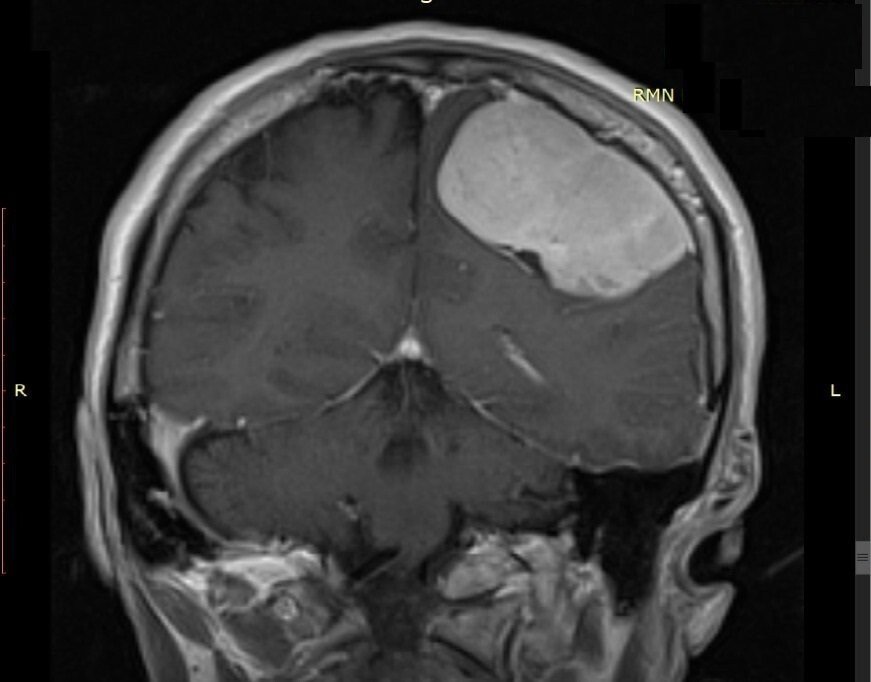

„Pacientul a fost internat ieri prin Unitatea de Primiri Urgențe, fiind diagnosticat cu o tumoră cerebrală gigantă care îi punea viața în pericol, prin comprimarea creierului. I s-au efectuat analize medicale, inclusiv testul pentru COVID-19. După studierea atentă a cazului am decis intervenția chirurgicală și am practicat rezecția completă a tumorii care a avut o mărime de 6/5 cm”, explică Șef Lucrări Dr. Vicențiu Săceleanu.

Intervenția chirurgicală, efectuată cu microscopul operator performant din dotarea secției, a durat aproximativ 4 ore. Operația a fost un succes și urmează ca pacientul să fie suspus unor controale post operatorii amănunțite.